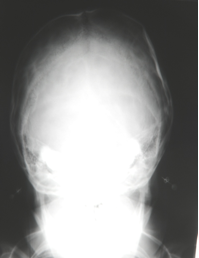

O que pode ser bem visualizado no Rx AP/PA?

Região frontal e órbitas. Se o Rx for bem feito pode-se visualizar estruturas do ouvido interno dentro das órbitas.

Sutura Sagital, Sutura Occipital, Órbitas, Septo Nasal, Cavidades Nasais